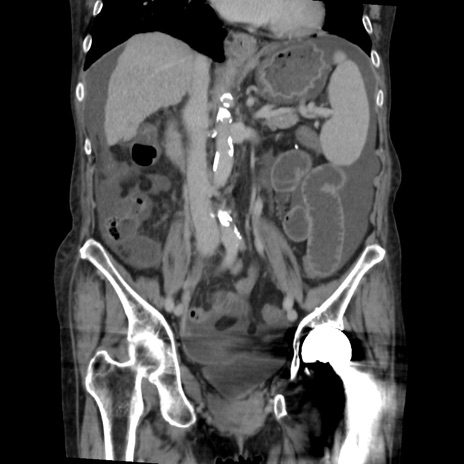

症例31(冠状断像)

【症例】80歳代 女性

【主訴】腹部膨満感

【現病歴】他院にて肝硬変にてフォロー中。1週間前から便秘、腹部膨満感、臍部腫瘤あり受診となる。

【既往歴】肝硬変

【身体所見】腹部膨隆あり、皮膚変化なし、疼痛なし。

【データ】WBC 4600、CRP 0.25